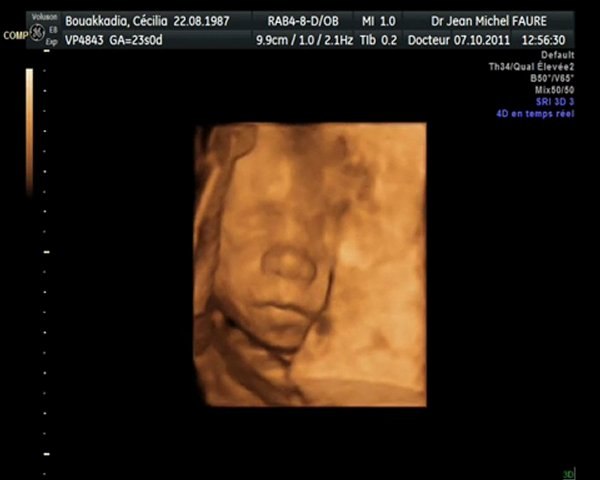

Echographie 3eme Trimestre 3d

Post A Photo Des Echo Du Troisieme Trimestre Venez Ici